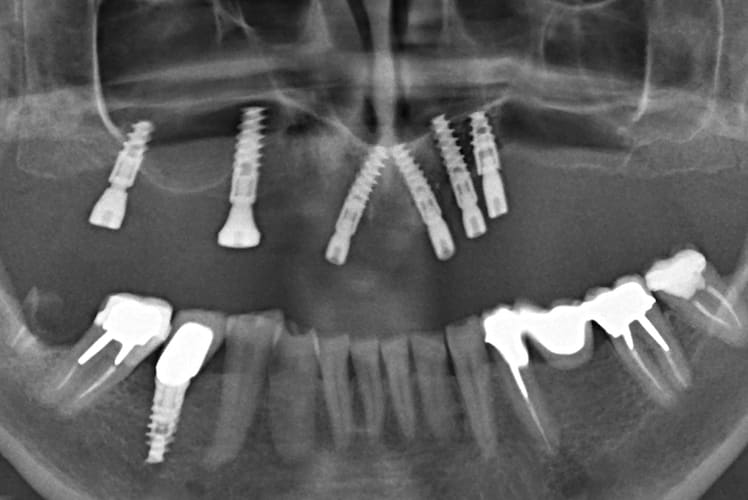

Vos suggestios seront les bienvenues.

Ce n'est pas un implanto qui me l'envoie, mais un correspondant ( je suis implanto non exclusif).

On peut légitimement envisager une dépose de l'ensemble, des greffes puis un autre plan de traitement sérieux. J'essaie dans la mesure du possible de faire avec ce qu'il y a.

Il lui a été proposé une prothèse conjointe qui me paraît infaisable.

Une prothèse type " sur pilotis" idem à cause du type d'implant qui ne permet pas cela et de l'absence totale de parallélisme.

J'étudie une possibilité de prothèse adjointe sur barre.

si çà peut aider, les implants sont des Naturactis ETK....